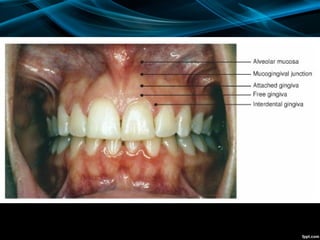

Gingiva (Gum(

1. Attached gingiva: It is firmly bound to the

2. Free or unattached gingiva: It is the distal 1

mm margin of gingiva that surrounds the neck

of the tooth and is not attached to the bone.